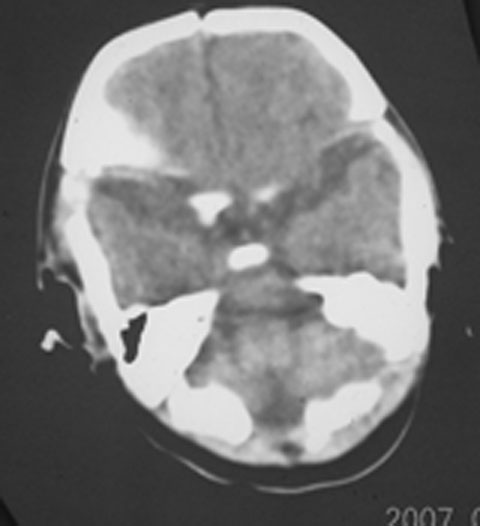

以下是引用rjg199343在2007-1-24 23:08:00的发言:[br]纵裂池、小脑幕、双侧脑室内高密度影,符合脑室、蛛网膜下腔出血。

以下是引用jiangjing在2007-1-24 23:31:00的发言:[br]纵裂池、小脑幕、双侧脑室内高密度影,符合脑室、蛛网膜下腔出血